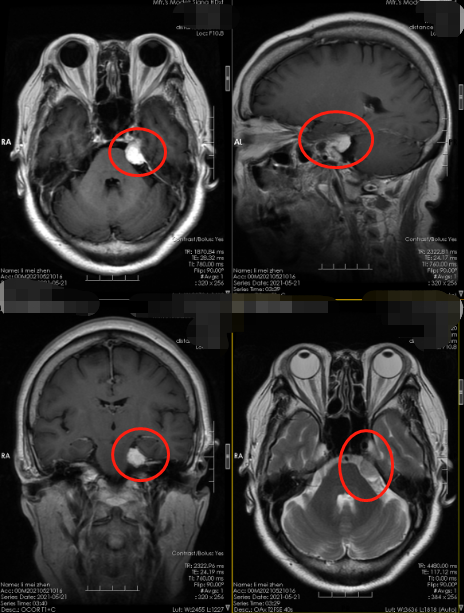

63岁的李阿姨最近半月左侧脸觉得有点麻木,偶尔出现头痛,但未在意,觉得是年龄大了,总是会有这样那样的小问题。最近左耳偶有耳鸣,总觉得听不清楚,去医院检查未发现耳疾,医生建议做头颅CT,李阿姨同意了,结果检查提示:左侧桥小脑角占位性病变。医生说桥小脑三角是指脑桥、岩骨、小脑之间的间隙,位于后颅窝的前外侧,是由前内侧的桥脑外缘、外后方的岩骨内缘及后下方的小脑半球前外侧,是一个锥形窄小的空间,此区的重要性在于集中了听神经、面神经、三叉神经及岩静脉、小脑前上动脉等重要的神经、血管,且好发肿瘤,尤其是听神经瘤。李阿姨的症状就是因为肿瘤压迫到面神经和听神经,所以出现脸麻和听力下降的症状,最好的治疗方案就是及早的手术,切除肿瘤。

▲术前